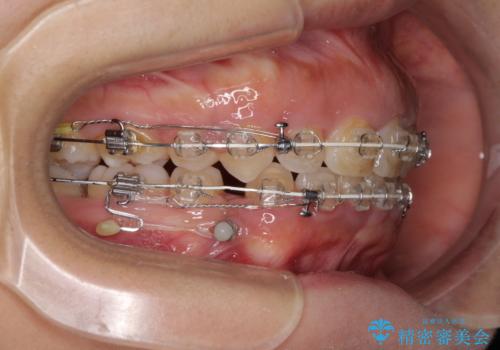

- 矯正装置

- 審美装置

- 口元の突出感と口の閉じにくさを気にして来院された患者様です。

上下左右の小臼歯4本を抜歯し、ワイヤー装置にて口元を引っ込めるよう矯正治療を行うこととしました。

上下顎ともに前突しており、特に上顎は著しい突出感でした。

また、下顎歯列には左右差があり、非対称な抜歯が必要と判断されたため、治療は困難なものとなりました。